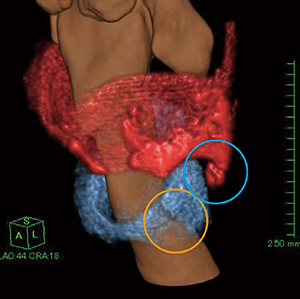

セミオート抽出機能を使用して,甲状軟骨,輪状軟骨,披裂軟骨の抽出処理を行ってVR画像を作成し,さらに気道のVR画像と重ね合わせて喉頭軟骨部の三次元画像を作成した。それぞれの部位でトレースして抽出処理を行うシンプルな作業なので,比較的短時間で画像を作成することが可能である。

作成したVR画像にて,甲状軟骨左下角に骨折があるのが確認できた(図4○)。また,輪状軟骨の左側壁部に線状影があり骨折しているのが確認できるが,オパシティ設定が難しく骨折部の明瞭な描出は困難であった(図4○)。輪状軟骨は低コントラストな物体であり,微細で複雑な形態を有するため,薄いスライスの情報が必要となる。そのためノイズが増加してしまい,画像に影響を及ぼしていると考えられる。

図4 セミオート抽出機能を使用して作成した喉頭軟骨VR画像

甲状軟骨左下角の骨折(○)を認める。また,輪状軟骨の左側壁部に線状影(○)があり骨折しているのが確認できるが,骨折部を明瞭に描出するのは困難である。

そこで,3Dフィルタを使用してオリジナル画像のノイズを低減させて,ボリュームの辺縁を滑らかに表示させる処理を行った。調整率によってフィルタのかかる割合が細かく設定でき,容易に画像確認を行うことが可能である(図5)。3Dフィルタによりノイズが低減されて辺縁が滑らかになったことで,輪状軟骨の左側壁部の骨折がより明瞭になり,内側に偏位しているのが確認できる(図6)。

図6 3Dフィルタを使用した喉頭軟骨VR画像